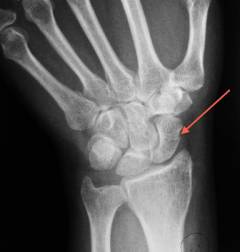

Переломы костей запястья возникают при падениях и приводят к боли. Наиболее часто встречается перелом ладьевидной кости.

- Перелом ладьевидной кости. Часто у молодых людей, медленно заживает.

- Перелом полулунной кости. Происходит при падении на руку с отведенной кистью.

Боль в запястье может быть вызвана переломами как костей запястья, так и дистального отдела предплечья. Наиболее частая причина — падение на вытянутую руку. Реже травмы происходят от прямого удара или сжатия. Перелом ладьевидной кости фиксируется в 60-70% случаев.

- Ладьевидная кость. Переломы этой кости чаще встречаются у молодых людей и возникают при падении на вытянутую руку. Восстановление занимает 5-6 лет из-за риска аваскуляризации, связанного с анатомией артерий. Симптомы включают боль и ограничение движений в лучезапястном суставе. Перелом может быть вертикальным, косым или горизонтальным, стабильным или нестабильным. Пациенты испытывают боль, отечность в области «анатомической табакерки» и трудности при сжатии кисти в кулак.

- Полулунная кость. Перелом происходит при падении на руку с отведенной в локтевую сторону кистью. При пальпации области полулунной кости возникает сильная боль, движения кисти сопровождаются дискомфортом.

- Рентгенологическое исследование. Для точного диагноза достаточно рентгеновских снимков в двух проекциях. Рентгенограмма позволяет установить местоположение перелома, наличие смещения и степень этого смещения. Повторное исследование назначается для контроля заживления.